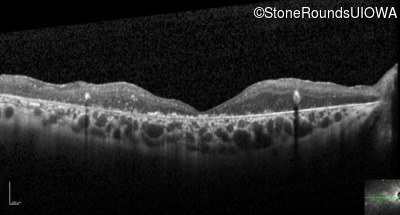

Optical Coherence Tomography - Right - 20/400 sc

Exemplar / OCT Stack